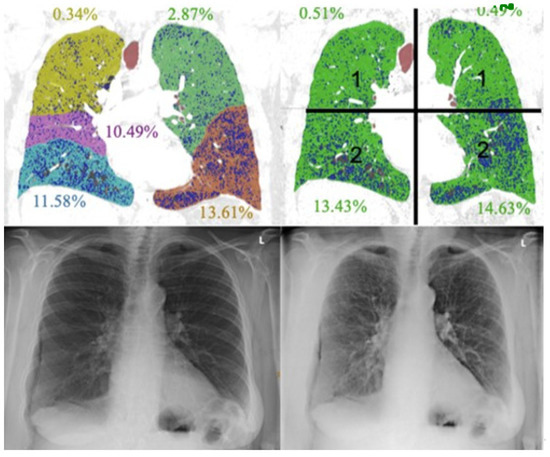

2.3.2. CT Image Analysis

3.2. CT Images: Standard of Reference

3.3. Presence of Emphysema

3.4. Emphysema Grading